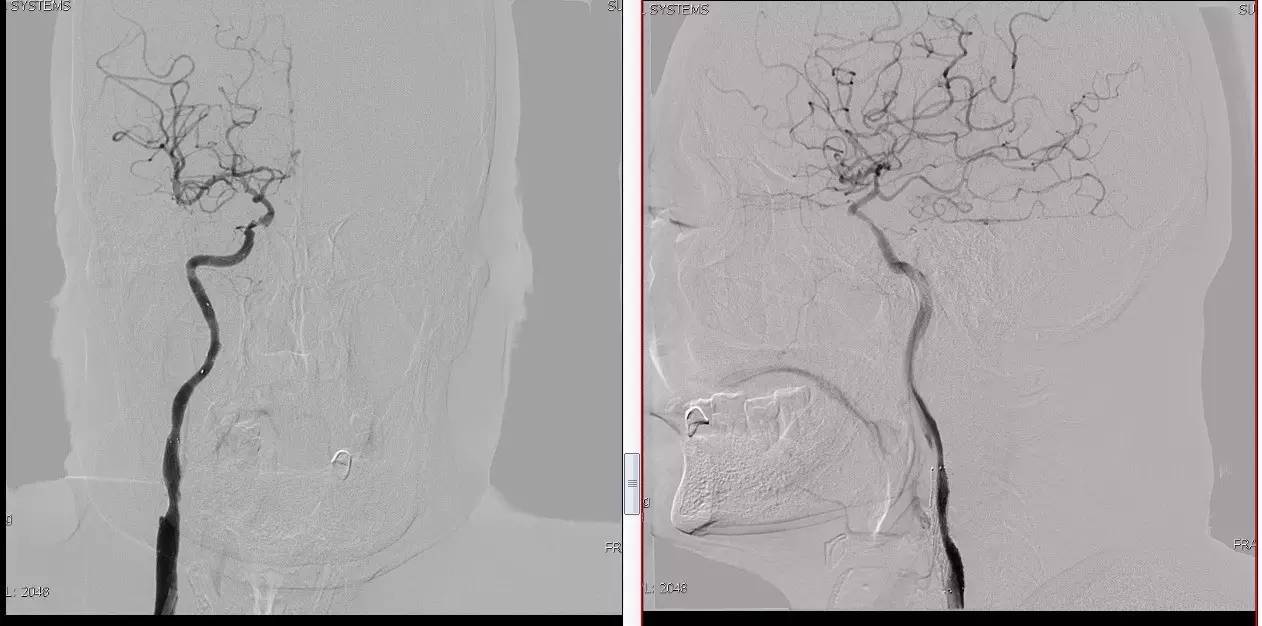

Case 2

》男,74岁。

》主诉:突发左侧肢体抽搐伴口角歪斜两月余,右侧肢体抽搐三天余。

》查体:左上肢肌力Ⅲ级,左下肢肌力Ⅳ级,右侧肢体肌力Ⅴ级。

》既往史:高血压病史。

》患者术后4小时出现右侧肢体无力,伴有癫痫样症状。

》考虑小栓子脱落,术中曾有后扩。